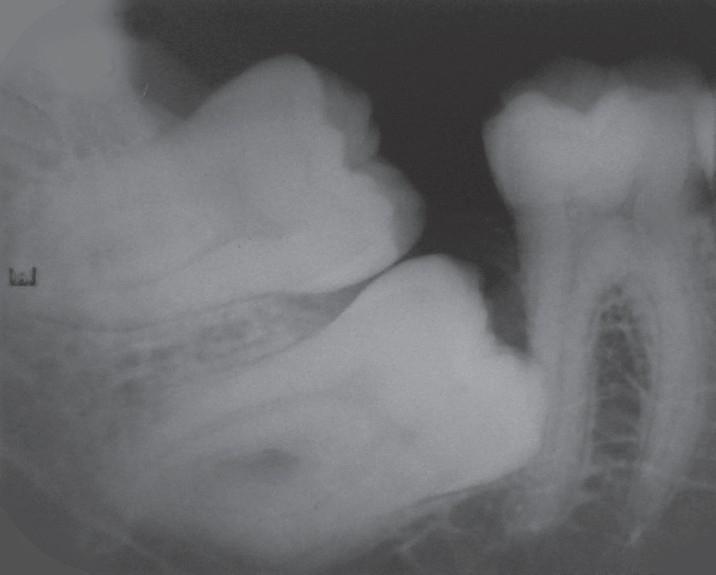

The impaction of permanent teeth is not uncommon, but few permanent teeth are rarely impacted like mandibular first and second molars. Though third molars are commonly impacted, inversely impacted mandibular third molars are very rare. Here, we report three unusual cases of impacted mandibular molars accidentally diagnosed on conventional radiographs.

Variations in impacted mandibular permanent molars: Report of three rare cases.